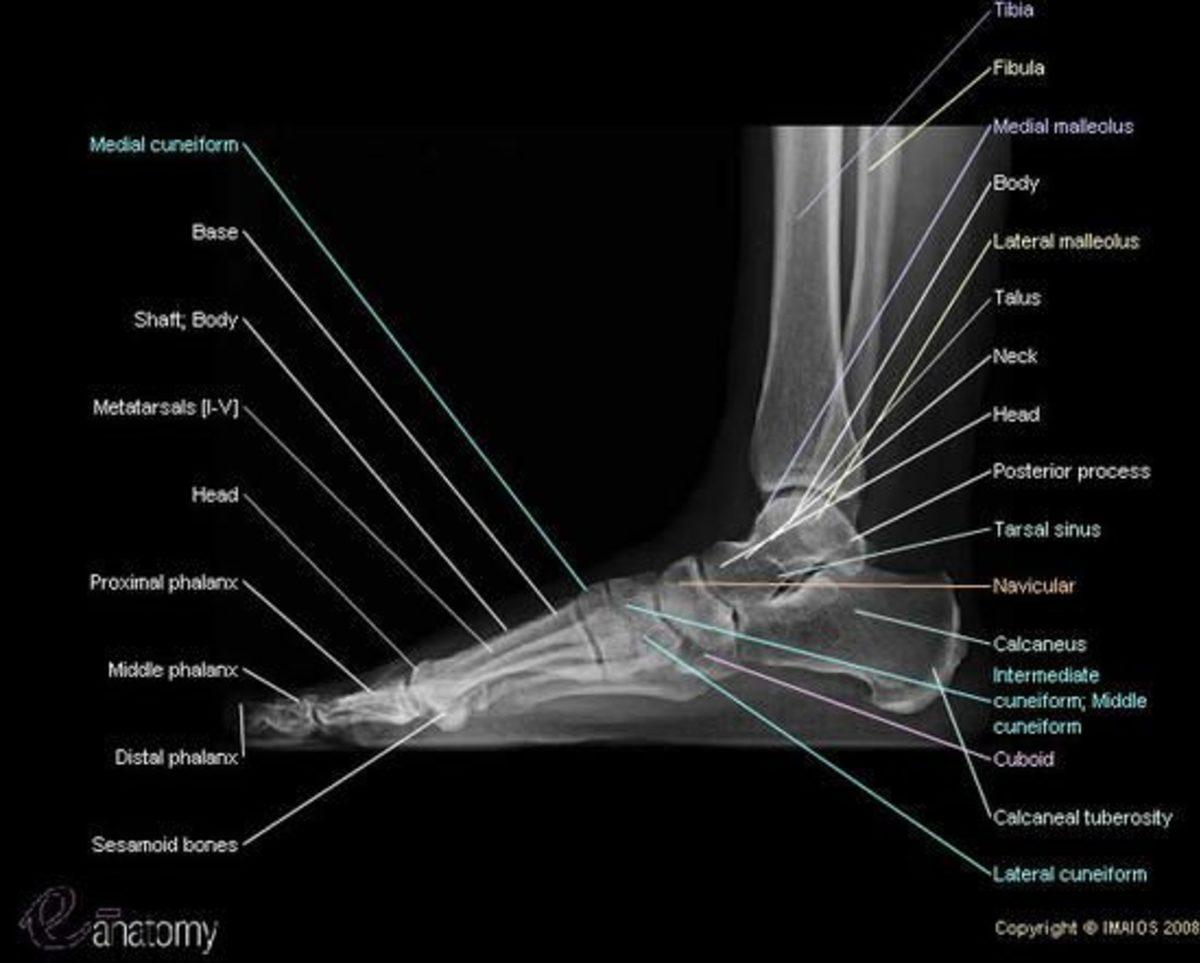

Yetişkin bir insanın tüm kemiklerinin dörtte biri ayaklarındadır

Ayaklarımızın vücudumuzun kalanına oranla pek de büyük olduğunu söylemesek de aslında ayağımızda 28 farklı kemik bulunuyor. Bunun yanına eklemler ve tendonlar da eklenince iki ayağımızda toplam 56 kemik, 66 eklem ve 200’den fazla tendon ortaya çıkıyor.